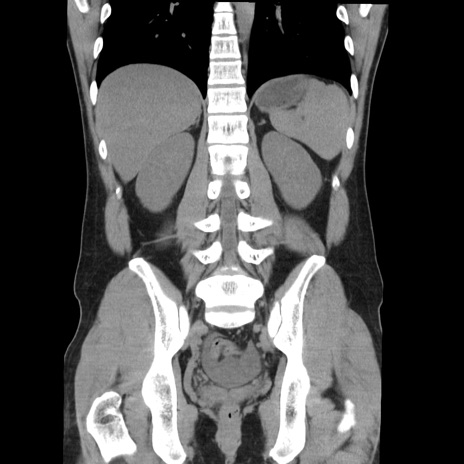

症例36(冠状断像)

【症例】20歳代 男性

【主訴】心窩部痛

【現病歴】今朝より上腹部痛あり。一旦軽快していたが再度出現したため救急要請。昨日夕に白身の魚を含む刺身を食べた。

【身体所見】BP 136/89mmHg、HR 74/min、BT 37.0℃、腹部:膨満、軟、心窩部に圧痛あり。反跳痛なし、筋性防御なし、腸雑音やや亢進あり。

【データ】WBC 17700、CRP 0.48